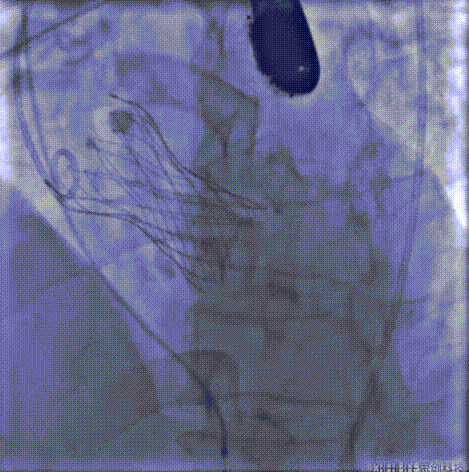

20mm球囊预扩,右无融合处钙化嵴被推开,造影显示无腰征微量造影剂渗漏